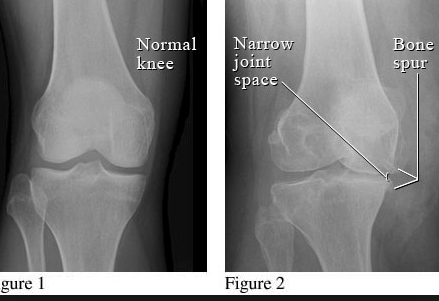

Classic signs of degenerative joint disease that can be seen on x-ray can be remembered using the acronym JOSS:

Joint space narrowing

Osteophytes

Subchondral sclerosing

Subchondral cysts